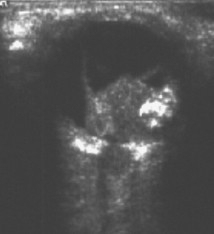

Ultrasound of retinoblastoma

Aerts I, et al. Orphanet J Rare Dis 2006 Aug 25; 1: 31; licensed under CC BY 2.0